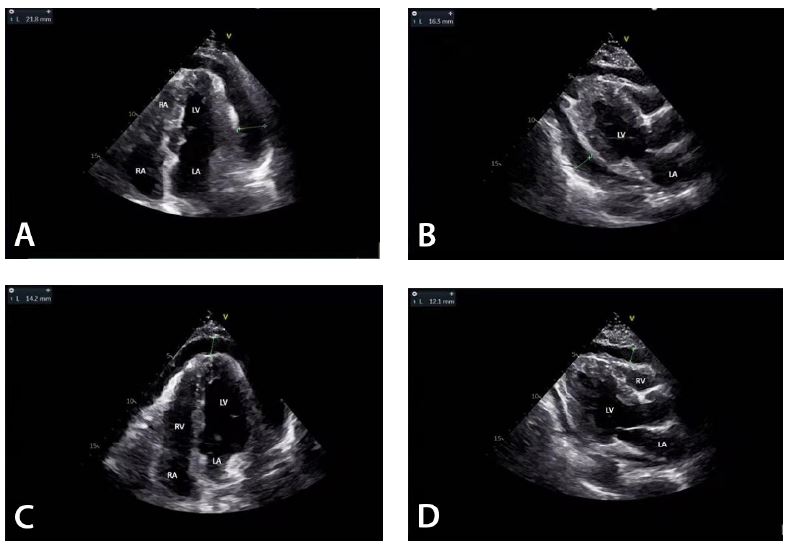

All pericardial drainages were performed with disposable sterile negative pressure groove drainage tube and guided by transthoracic color Doppler ultrasound. The coagulation profile and unsatisfactory bleeding profile were corrected before intervention in all patients. All patients were placed in supine position (Figure 1A), and then, the location of effusion and/or associated pericardial thickening was confirmed under the guidance of bedside color Doppler ultrasound by the surgeon (Figure 2). Complex iodine was used to disinfect the median sternal incision, pericardium, and mediastinal drainage tube. A conventional sterile draping was placed (Figure 1B). 0.2% lidocaine was subcutaneously injected to anesthetize the skin and subcutaneous tissues of the mediastinal and pericardial drainage orifices. A 2.6-cm sterile Loach guide wire (Terumo, Tokyo, Japan) was placed through the routinely indwelling mediastinal and pericardial rubber drainage tubes during operation (Figure 1C). The indwelling pleural drainage tube and pericardial drainage tube were removed along the guide wire (Figure 1D), and then the catheter of the negative pressure groove drainage device was placed along the guide wire (Figure 1E). The position of the drainage tube was adjusted under the guidance of color Doppler ultrasound, and then, set off to slowly drain. After the drainage tube was fixed to the skin at the initial drainage orifice by two regular stitches, the drainage bottle (Sanrui, Jiangsu, China) was connected. Complex iodine was used to disinfect the incision two times. Sterile dressing was used to cover the incision. The same procedure was performed on the opposite side (Figure 1F).